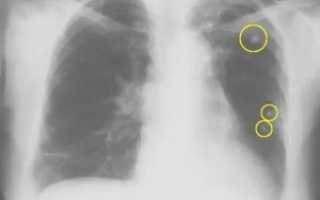

Флюорография лёгких определяет состояние органов грудной клетки, сосудов и сердца. На флюорографических снимках можно увидеть легочные заболевания, новообразования и воспалительные процессы.

Исследование лёгких позволяет вовремя обнаружить патологические изменения лёгочных тканей и может показать признаки сердечной недостаточности. Флюорограмма показывает внутренние органы в грудной области, их соединения. Рентгеновские лучи проходят сквозь тело человека и переносят на плёнку рисунок внутренних органов.

С помощью флюорографии легких можно удается выявить следующие заболевания:

• пневмонию;

• злокачественную опухоль;

• склероз;

• скелетно-мышечные отклонения;

• фиброз;

• сердечно-сосудистые болезни (увеличение, смещение сердца);

• грыжу;

• туберкулёз;

• кисты;

• абсцессы.

Также флюорография поможет обнаружить инородные предметы в лёгких или дыхательных путях.

Стандартная формулировка при выдаче заключения здоровому пациенту выглядит так: «Сердце и лёгкие без видимой патологии». В действительности, опытный рентгенолог рассмотрит на снимке и другие объекты.

Так, кроме главного органа дыхательной системы и тени сердца с перикардом, на нём видны позвоночник, диафрагма, часть пищевода, крупные бронхи.

Но наиболее информативна флюорограмма всё же только в отношении лёгких и сердца.

Полученное при помощи флюорографического аппарата изображение ОГК (органов грудной клетки) может дать исчерпывающие ответы о состоянии пациента или стать причиной назначения уточняющей диагностики, если есть на то основания. Даже на небольшом флюорографическом кадре для рентгенолога видны характерные следы, говорящие о том или ином заболевании.